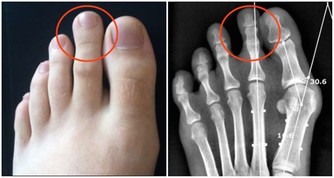

一般心源性猝死分三種:

一種是器質性心髒病,最常見的是冠心病。多發生在年齡稍大的男性身上,他們多伴有糖尿病、高血壓等慢性疾病,同時愛抽煙,長得胖,特別是在激動狀態下容易發生胸悶胸痛,引發猝死,還會在運動、生氣、氣溫驟降的情況下發生;